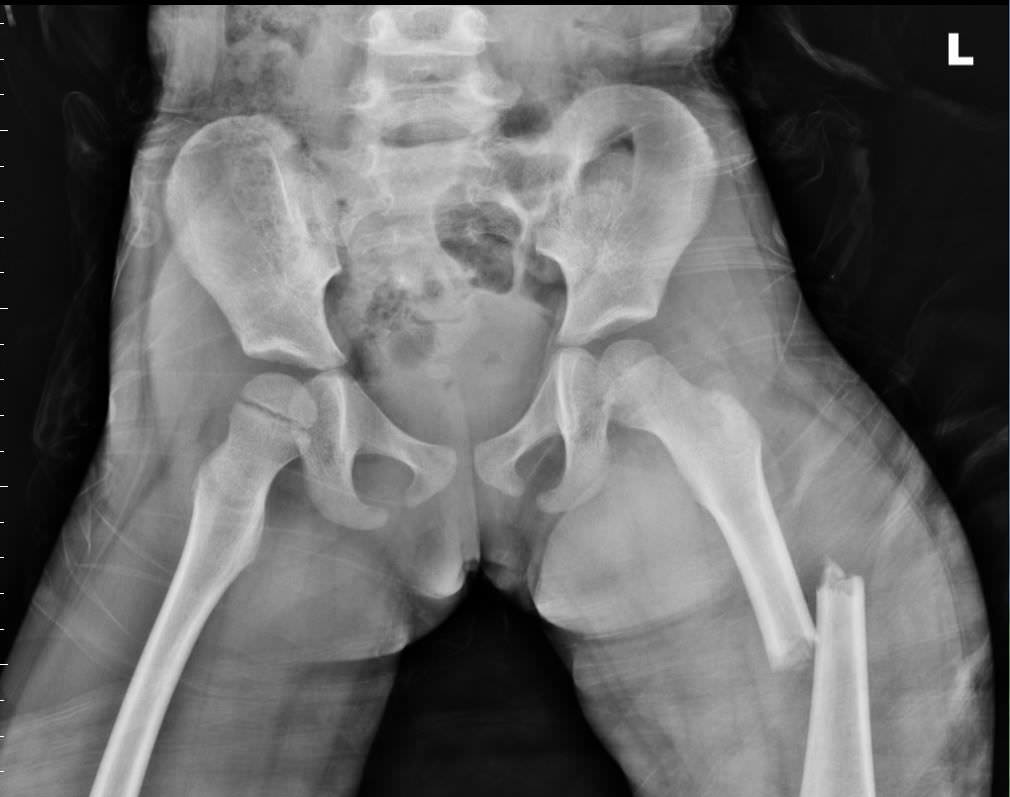

意外伤害是儿童死因的第一名,大部份是跌落与交通事故伤害。我们不断地强调「安全座椅」,是因为这是最重要的防护。发生交通事故时,安全座椅的使用与否,死亡率有八倍的差异。还有许多居家与出外安全的提醒。下图是最近一个发生的事故。三岁孩子放在机车前座,车祸时,大腿骨折。